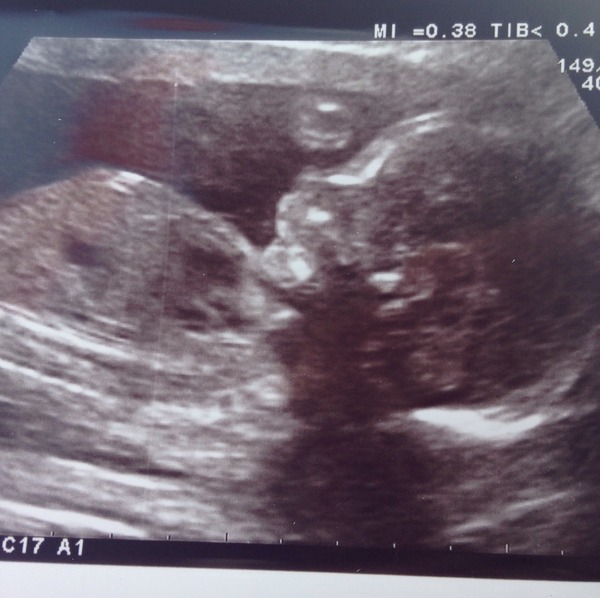

Just realised that pic has got my name on it. Have reported it! Good pic though!!

Right, I'll try again!

Had 20 week scan today. It all went really well - everything measured perfectly and all organs were doing what they should! Very happy. Starting to get more excited now!

Aww beautiful pic Fizzy Smile

Lovely scan news kep and fizzy! Glad all's looking good for your little ones.

Oh also, congrats fizzy on a good scan too!! And a lovely pic Smile

The only difficulty I'm having with the hack is that I can't login to the apps as they keep saying they are offline - it has gone pretty quite on MN. I think it's quite nice to move onto a Facebook group after our babies are born though, as then we can keep our lovely children photos between us rather than the whole internet. Just now we just have scan pictures (which all look the same really) and headless bump photos, so it's not going to 'out' any of us.

Aww Fizzy lovely picture Smile